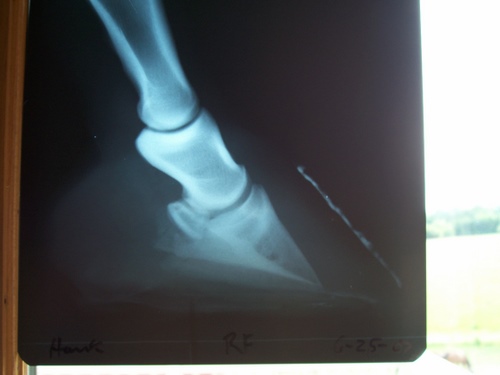

Posted on Monday, Jul 9, 2007 - 2:29 pm: Dr.O I went and got Hanks X-rays and would appreciate any input you have. I have to do something soon with his hooves and I haven't heard anything from the 2 farriers that have dealt with this. I may have to go with my regular inexperienced farrier, so any input will be greatly appreciated!As I said before not the greatest x-rays, but it's all I have. I think the left front got taken at an angle, I can't remember what the vet said how it happened. I think the block turned a little if I recall. Left front Right front

Posted on Monday, Jul 9, 2007 - 7:10 pm: Oh Diane, I'm anxious to hear what Dr. O says, but from the radiographs, I'd say he really needs a farrier experienced with rotated horses and theraputic trimming/shoeing. I'm sorry you haven't heard back from your prospects! Only four weeks? Those toes are really long. I think if his breakover could be brought back to the proper alignment with the tip of the coffin bone, possibly removing some underrun heel and a natural balance shoe PROPERLY placed (perhaps with a wedge pad after the removal of some heel) the alignment would look better and you'd have a start on derotation. It's hard to tell from the radiographs how far the tip of his coffin bone is from the surface, and that's an important piece of info. The NB shoe has a wide toe with the inner rim that sort of arcs toward the frog to protect the tip of the coffin bone, but it must be placed properly--that's very important--and isn't the same as traditional shoe placement. Boy, I wish I could send you my farrier. He's sort of a guru with horses like Hank. I feel blessed to have him as do the area vets!!! |

Posted on Wednesday, Jul 11, 2007 - 6:18 am: Looking at the radiographs, I think that sounds reasonable Diane.DrO |

Posted on Monday, Jul 16, 2007 - 7:31 am: Diane, these are decisions that will have to be made by examining the foot, follow your veterinarian and farriers recommendations.Concerning your earlier questions about the radiographs there appears to be moderate rotation present and there is nothing in the radiographs to suggest permanent lameness. DrO |

Posted on Wednesday, Sep 5, 2007 - 4:39 pm: Dr.O. I read the article again and it seems that is what we are doing, the farrier is rolling the toe and setting the shoe back so when he walks there is no torque at the toe.The one thing that confuses me is the hoof pastern angle. When looking at the radiographs above in this post does it appear Hanks is OK.? In the article where the pics are the coffin bone seems more pointed down? If his angle is OK how do you de-rotate? Thanks |

Posted on Sunday, Oct 21, 2007 - 10:50 pm: Dr.O. I came across some x-rays of a horse that were very similar to Hanks. I know the above rads are bad but something has been hitting me as "strange" since viewing them. Most rads I have seen of foundered horses show the coffin bone pointed down.....like the picture in step one of the derotation article.Hanks coffin bone seems to just sit lower in the hoof wall with really not much if any pointing down. Does this indicate anything like sinking? I'm starting to wonder if these terrible radiographs make his hoof look way worse than it truly is ???? Can you give me any insight on this? Thanks |

Posted on Monday, Oct 22, 2007 - 8:18 am: You really cannot tell from the above images Diane without the bottom carefully marked with something radioopaque, like a thin wire taped to the middle of the board the horse is standing on. If with well marked radiographs the bone still seems close to the ground, it may be the soles are thin.DrO |